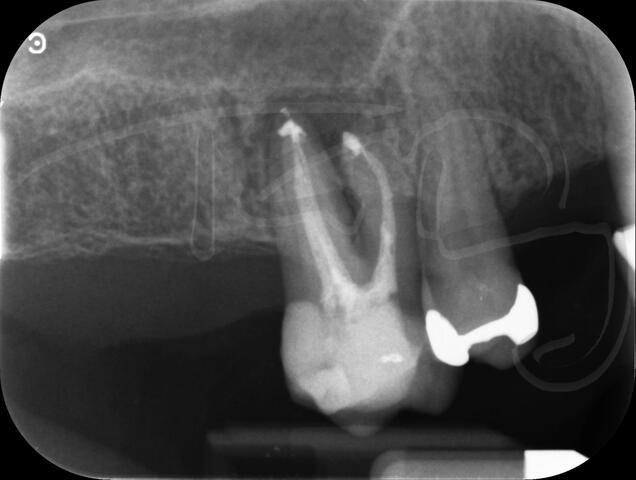

I really enjoy undertaking root canal treatments - rising to the challenge and helping people out of dental pain for the long term.I was privileged to be asked to speak at the 2016 BDA Conference, where I have a lecture about providing quality endodontic outcomes to patients, working as a generalist. Avoiding problems and pitfalls and maximising efficiency. One of the main matters that he covered was understanding that what is seen on plane radiography is utterly misleading and should not be the criteria by which a generalist continues treatment once it has been started.

At the 2016 BDA Conference, Thomas spoke about providing quality endodontic outcomes to patients, working as a generalist. Avoiding problems and pitfalls and maximising efficiency. One of the main matters that he covered was understanding that what is seen on plane radiography is utterly misleading and should not be the criteria by which a generalist continues treatment once it has been

started.